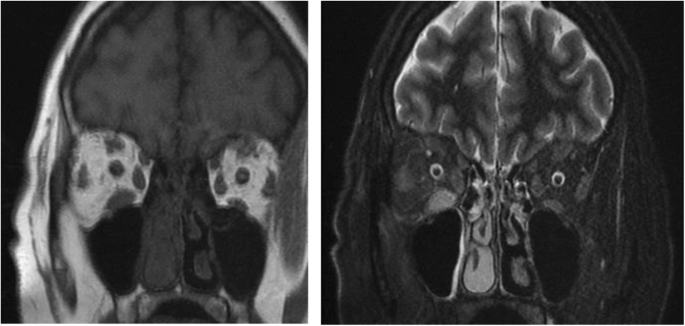

The initial biological investigation was followed by a cerebral and orbital 1.5 Tesla Magnetic Resonance Imaging (MRI) under sedation for claustrophobia, which revealed a tumefaction and edema of the extraocular muscles including the right inferior and right lateral muscle and to a lesser extent the left inferior orbital muscle with slight infiltration of the orbital fat and inflammation of the periorbital soft tissue especially to the right (Fig. 2). Optical nerves were of normal thickness and signal. Imagery findings were suggestive of an orbital inflammatory pseudo-tumor.